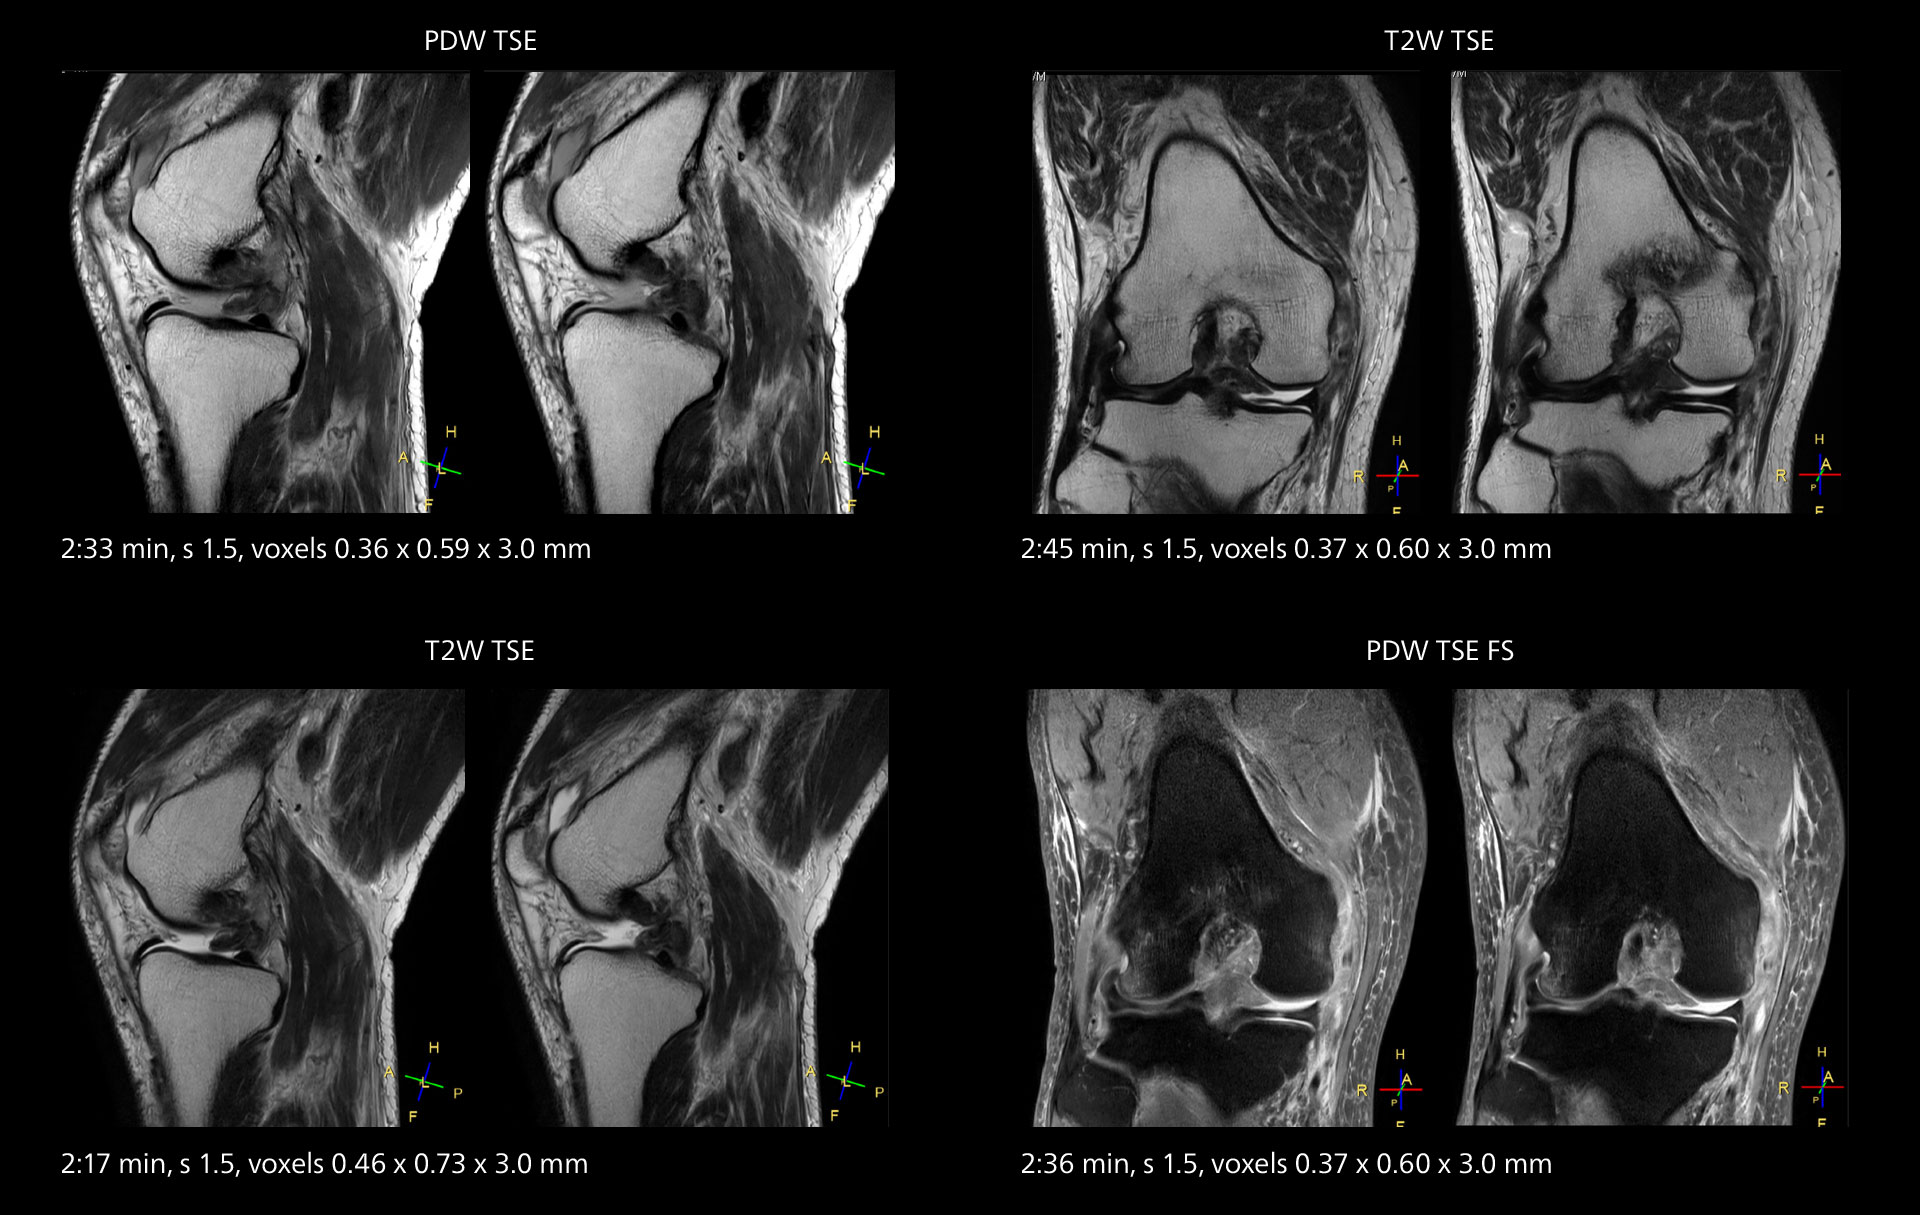

An example of increased imaging speed is in knee studies. “There is a definite scan time reduction for T2* mFFE and proton density TSE – both of these sequences benefit from much shorter repetition times,” he reports.

MRI of the knee

Images showing a posterior cruciate ligament (PCL) tear, a detached medial collateral ligament (MCL) on the tibial side and an intact anterior cruciate ligament (ACL). SmartPath to Elition X helped reduce scan time compared to previous imaging while maintaining resolution.

Overall, imaging time per sequence has been reduced since the Elition X upgrade. This can help reduce the risk of patient movement and the need for rescans.